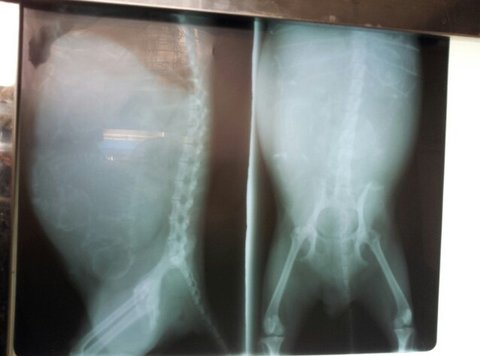

저 배에 탄탄군과 동생들이.

고생하신 탄탄군 어머니.

탄탄군 아버지~